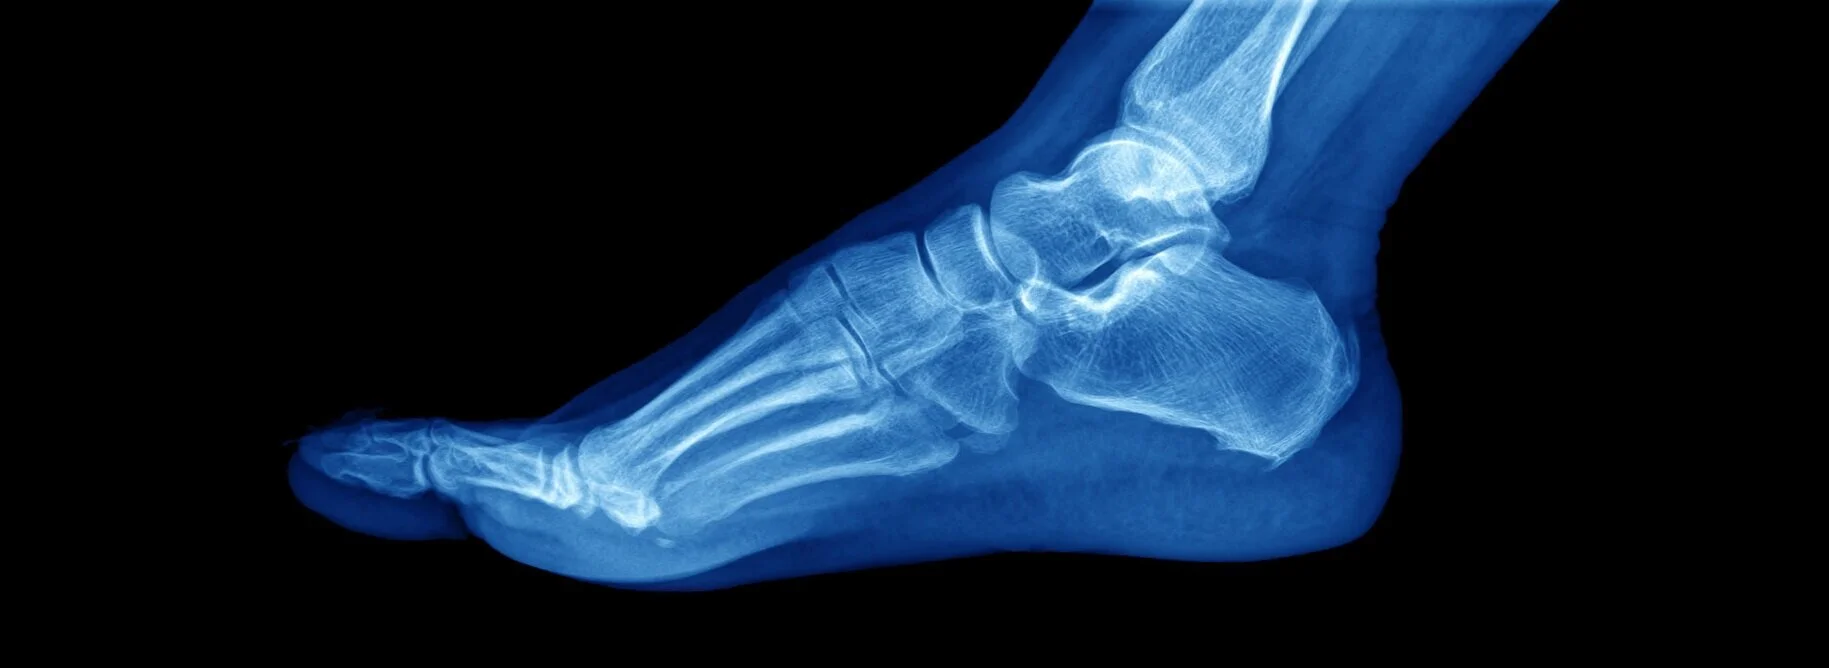

General X-ray is a widely used medical imaging technique that provides valuable insights into the internal structures of the human body. It involves exposing a part of the body to a controlled dose of ionising radiation, which is then captured on a special X-ray-sensitive film or digital detector. These X-rays are typically invisible to the human eye but are absorbed differently by various tissues in the body, creating shadows or images that reveal the underlying structures such as bones, organs, and soft tissues. They are quick, non-invasive, and widely accessible, making them an essential tool for physicians to aid in diagnosis and treatment planning.